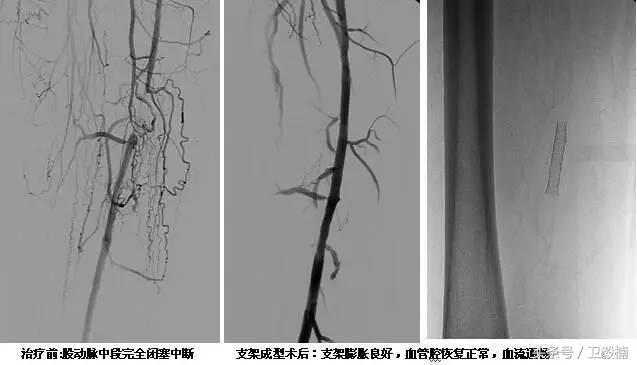

3、经皮腔内血管成形术(Percutaneous transluminal angioplasty,PTA)

60年*开代**始应用于动脉,使狭窄的血管扩张,70年代研制双腔气囊导管成功后,得到广泛应用,多用于髂、股、腘动脉及肾动脉。肾动脉PTA(或PTPA)多用于肾源性高血压,使狭窄肾动脉扩张,从而降低血压。PTA亦可用于冠状动脉,称为经皮腔内冠状动脉成形术(Percutaneous transluminal coronary angioplasty,PTCA),使硬化的冠状动扩张,以达到治疗冠心病的目的。PTA使用的导管为带胶囊的双腔导管,将胶囊段置于狭窄血管处,囊内注入含有造影剂的液体,加压至3~6个大气压,每次持续10—15o。加压可重复3~4次,多数能使狭窄血管达到扩张的效果。

PTA多用于动脉粥样硬化性狭窄的血管,其机理是粥样斑块受压,内膜和中层撕裂、伸展,使管腔增宽。其他原因的血管狭窄,如多发性大动脉炎,先天性血管狭窄,有时也可用PTA治疗。